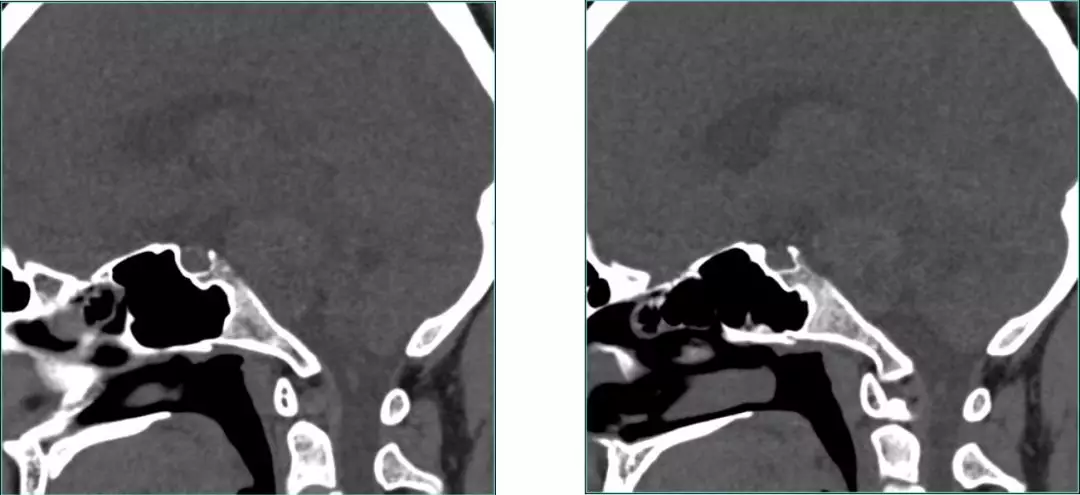

Pre-op CT scan

Pre-op CT Contrast